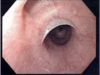

What is this infectious disease?

Necrotizing Gingivitis (NG)

o No periodontitis features

o SIMILAR APPEARANCE to gonorrhea

▪ Distinguishing characteristic of NG – Fetid Odor